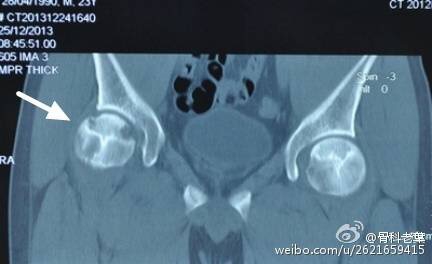

III期 磁共振出现异常,X线片显示软骨下塌陷(新月征),股骨头内出现空洞,股骨头没有变扁

II期和III期的患者治疗方法相同,因为此时股骨头虽然还没有变形,暂时还不需要行人工关节置换术,但是股骨头已经出现空洞,随时股骨头就会塌陷变形,所以单纯的股骨头减压术是不能达到治疗效果的。这时就需要在股骨头减压的同时,植入一根支撑棒,顶住股骨头空洞区,防止股骨头在负重的情况下过早塌陷。其他治疗同之前相同,口服以上药物,定期复查,密切观察病情发展,尽量避免重体力劳动和爬山爬楼。